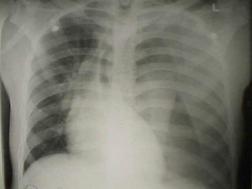

Pneumotorace sufocant bilateral Pneumotorace sufocant stang

Pneumotorace

sufocant stang Pneumotorace

sufocant drept Pneumotorace

sufocant drept

Imagine

CT Imagine CT